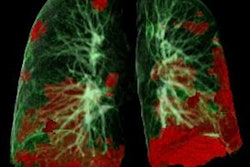

The SARS-CoV-2 virus tends to first affect a patient's respiratory system, but it can also damage the central nervous system. Physicians use electroencephalography (EEG) to identify brain injury caused by the virus, although sometimes the findings aren't conclusive. Fortunately, help is on the way: European researchers have discovered that adding MRI data to the mix of clinical information improves estimates of a patient's risk of developing COVID-19-related encephalopathy, according to a study we're highlighting in this edition's Insider Exclusive.